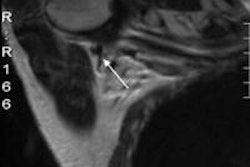

Invasive ductal carcinoma with positive axillary lymphadenopathy. The detection of malignant masses is relatively easy using DWI for both index tumor and axillary positive lymph node. ADC values of the index tumor and positive homolateral lymph node were less than 0.9. This case illustrates the usefulness of DWI to detect both index tumor and positive lymphadenopathy. Images courtesy of Dr. Isabelle Thomassin-Naggara.